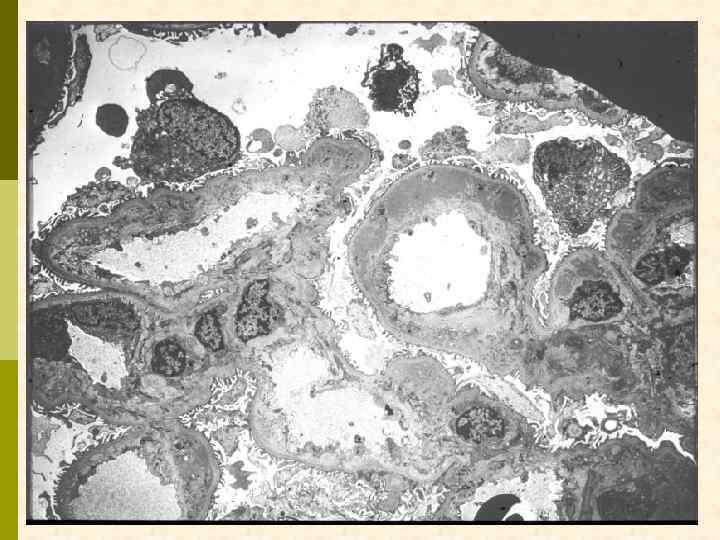

Гистологические варианты МПГН q Тип I – хроническая иммунокомплексная болезнь иммунные депозиты в мезангии и субэндотелии q нередко ассоциируется с гепатитом С, смешанной криоглобулинемией, гепатитом В, бактериальным эндокардитом q q Тип II – болезнь плотных депозитов q С 3 при иммунофлуоресценции, но без иммуноглобулинов q аутоантитела к С 3 конвертирующему ферменту (C 3 Nef) q в 90% случаев рецидивирует в трансплантате q Тип III – хроническая иммунокомплексная болезнь q в отличие от I типа имеются субэпителиальные депозиты и разрушение базальной мембраны с прозрачными лакунами

Гистологические варианты МПГН q q Тип I – хроническая иммунокомплексная болезнь q иммунные депозиты в мезангии и субэндотелии q ассоциируется с гепатитом С, смешанной криоглобулинемией, гепатитом В, бактериальным эндокардитом Тип II – болезнь плотных депозитов q q С 3 при иммунофлуоресценции, но без иммуноглобулинов аутоантитела к С 3 конвертирующему ферменту (C 3 Nef) в 90% случаев рецидивирует в трансплантате Тип III – хроническая иммунокомплексная болезнь q в отличие от I типа имеются субэпителиальные депозиты и разрушение базальной мембраны с прозрачными лакунами

Гистологические варианты МПГН q Тип I – хроническая иммунокомплексная болезнь q иммунные депозиты в мезангии и субэндотелии q ассоциируется с гепатитом С, смешанной криоглобулинемией, гепатитом В, бактериальным эндокардитом q Тип II – болезнь плотных депозитов q С 3 при иммунофлуоресценции, но без иммуноглобулинов q аутоантитела к С 3 конвертирующему ферменту (C 3 Nef) q в 90% случаев рецидивирует в трансплантате q Тип III – хроническая иммунокомплексная болезнь q в отличие от I типа имеются субэпителиальные депозиты и разрушение базальной мембраны с прозрачными лакунами